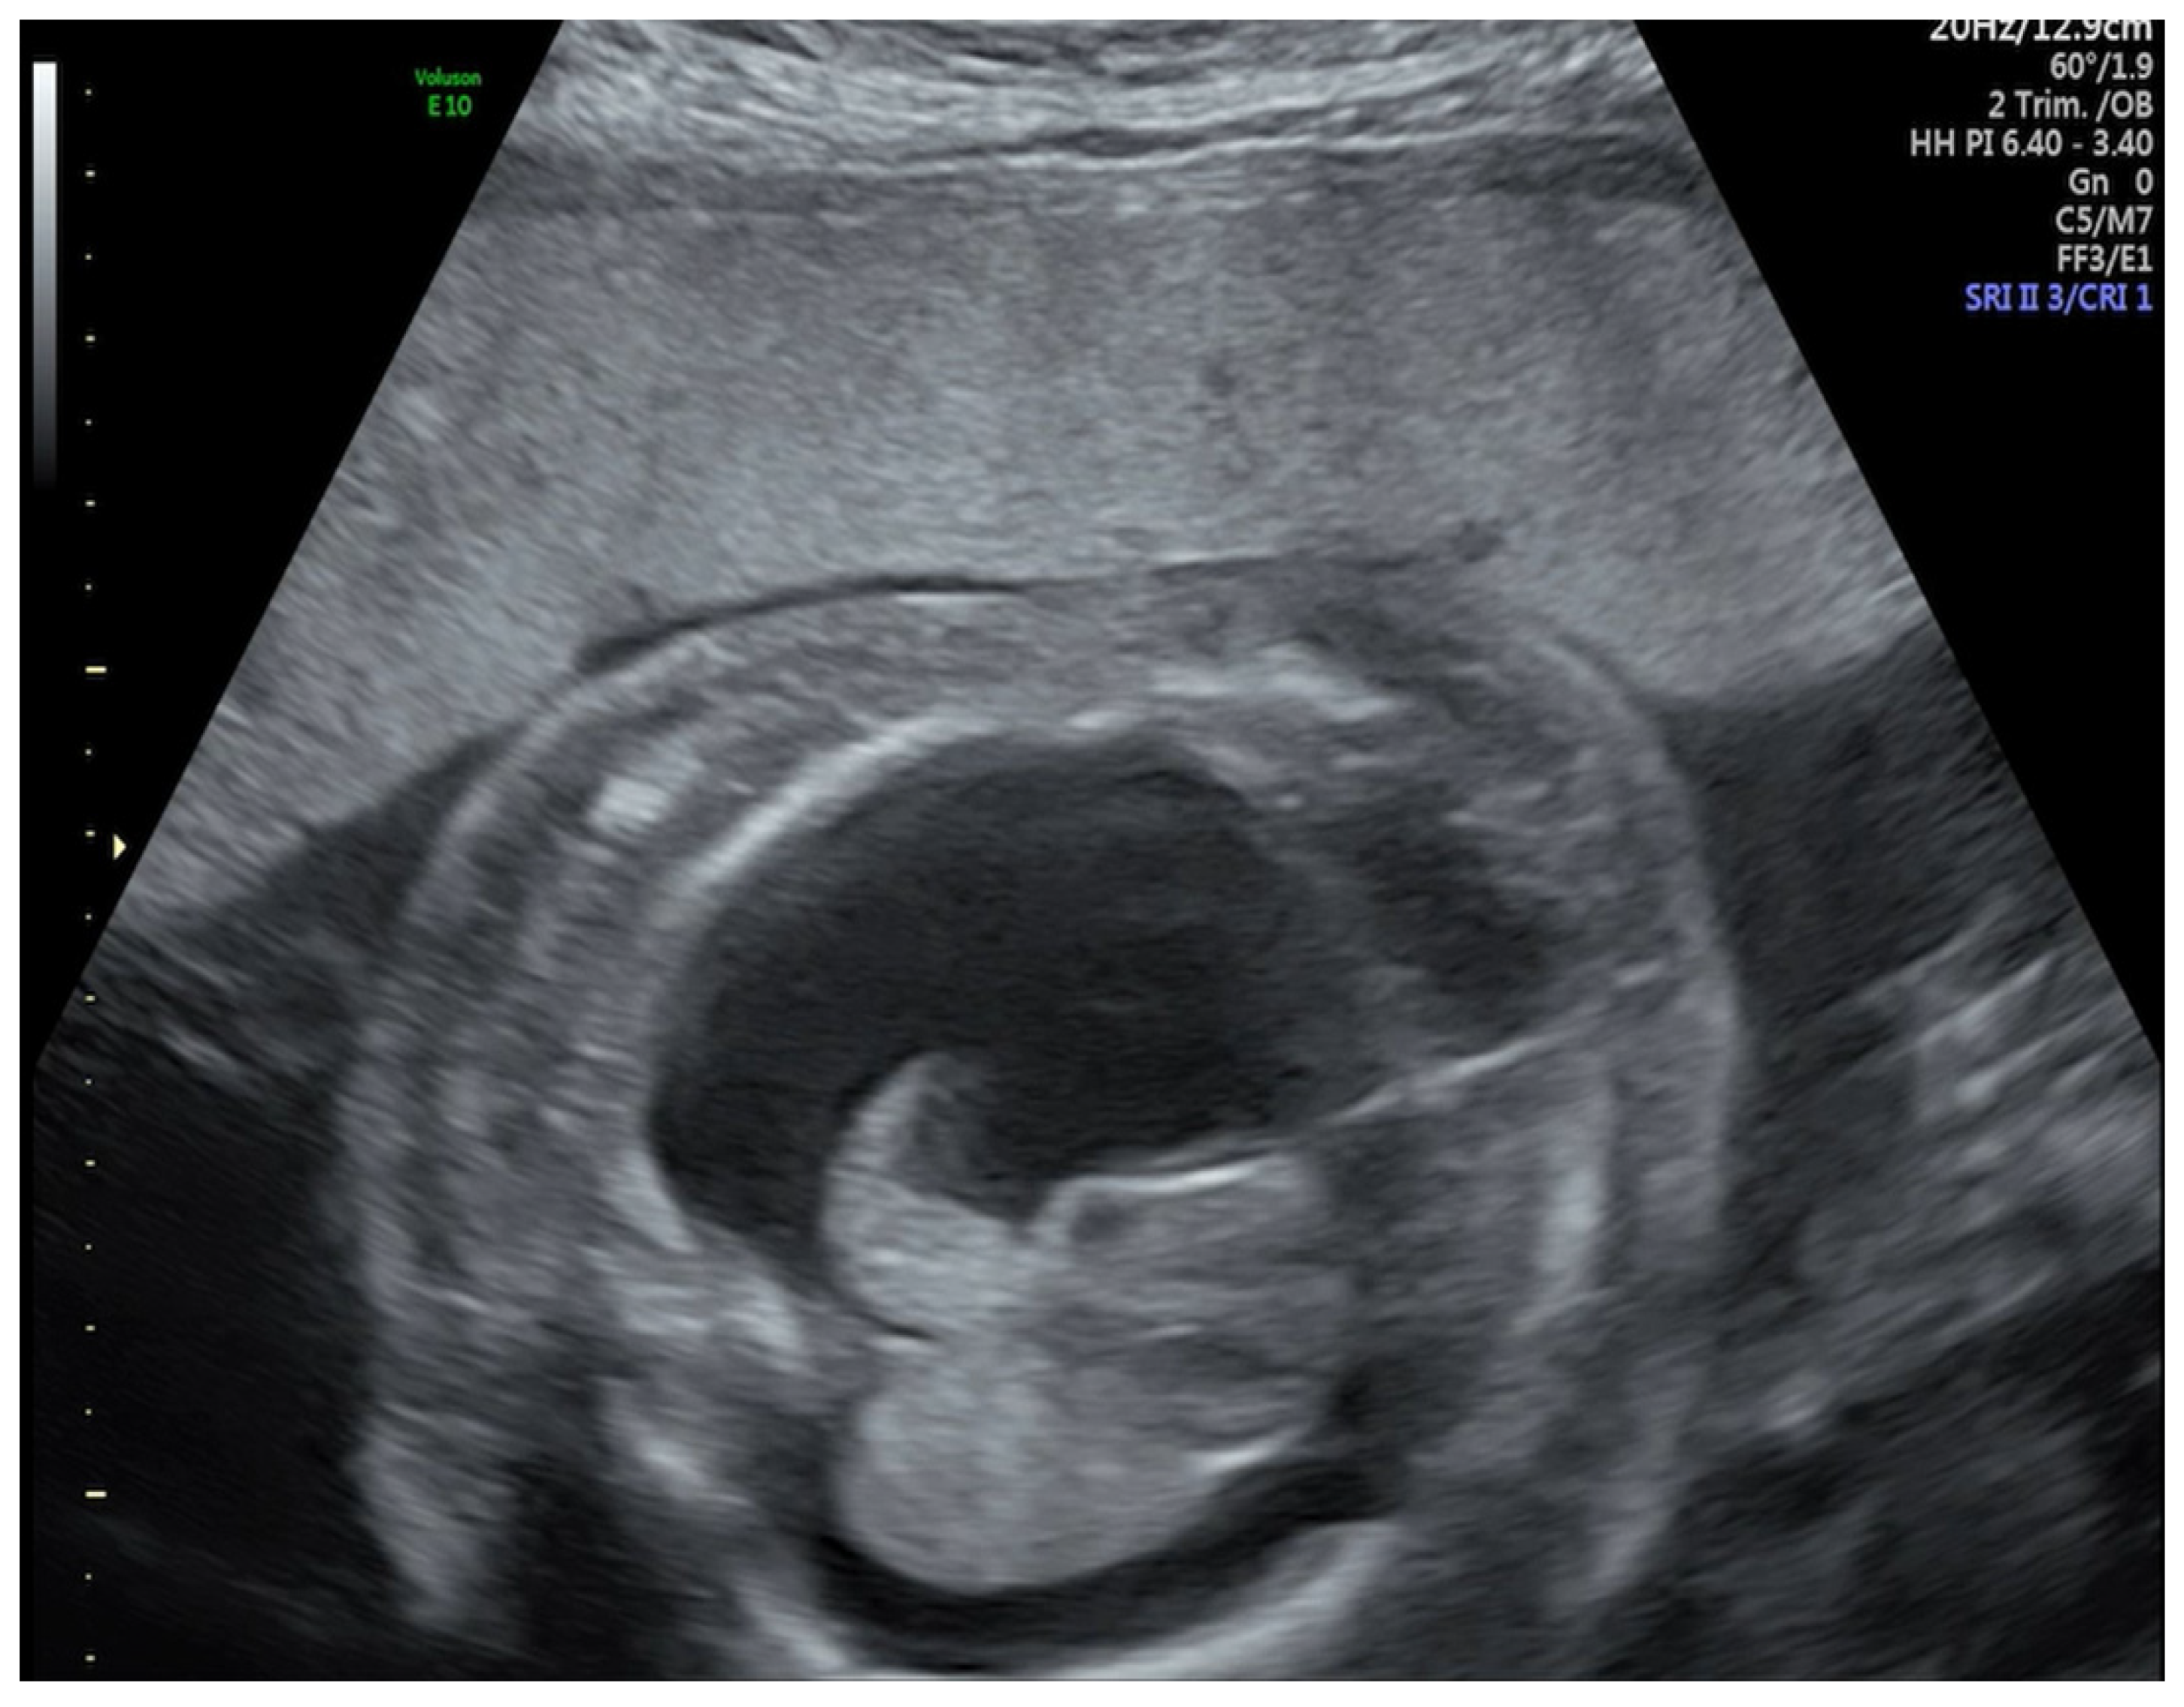

A Case of COVID-19 Pregnancy Complicated with Hydrops Fetalis and Intrauterine Death

2. Case Report